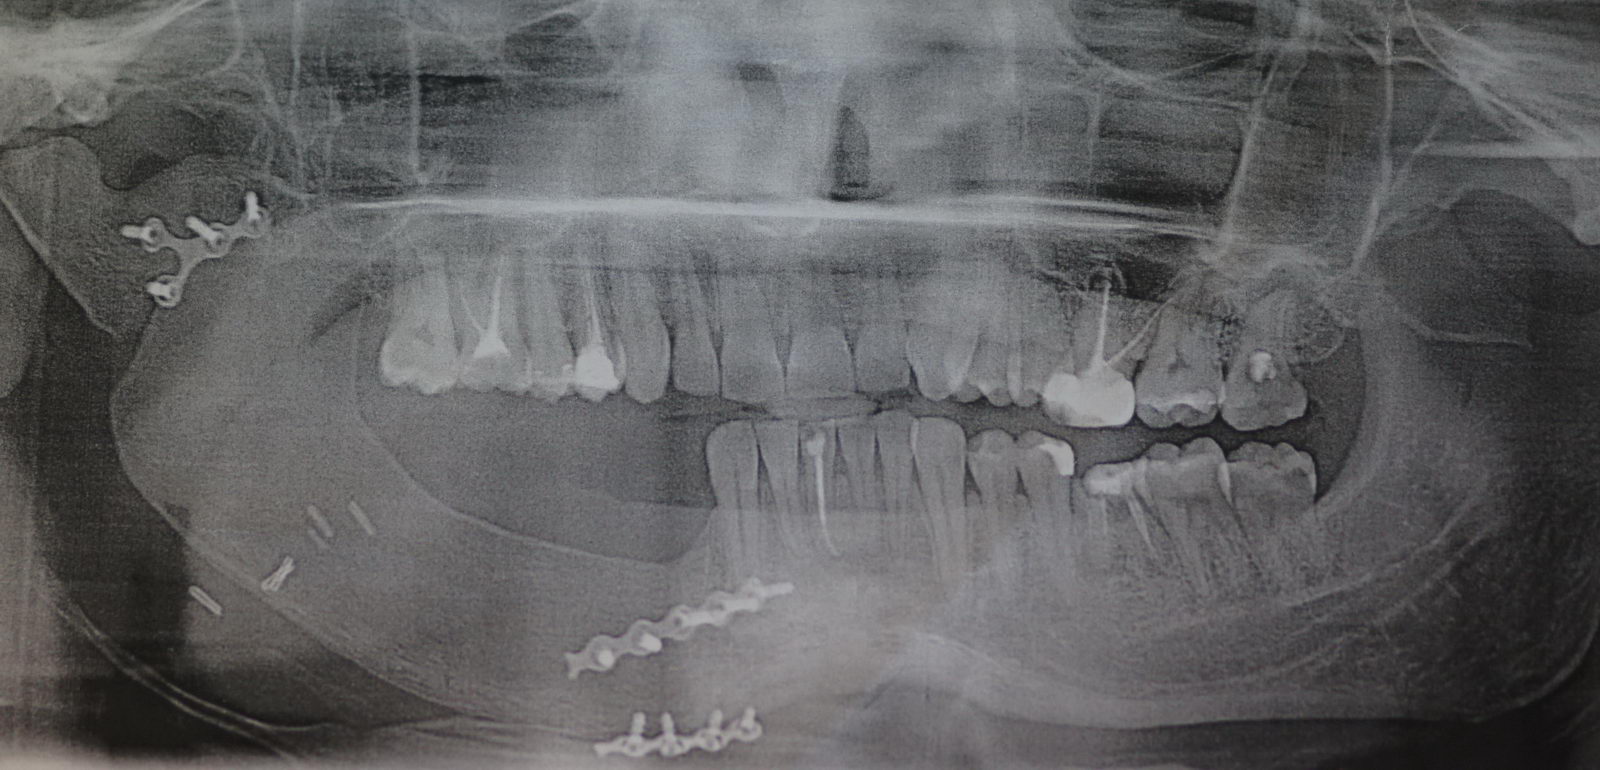

Медицинские Исследования: Кортикальная Пластинка на ОПТГ